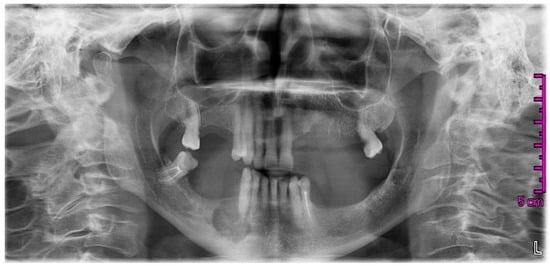

2. Case Report